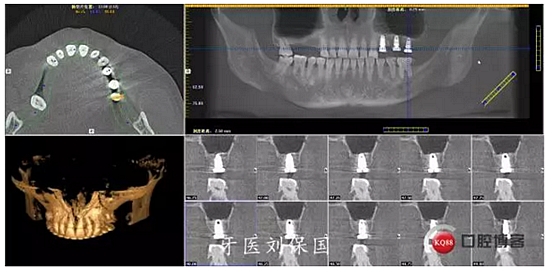

1.術(shù)前CT:

治療計(jì)劃及相關(guān)費(fèi)用已向患者講明,征得患者同意,口腔及頜面部常規(guī)消毒,鋪巾,5.1ml必蘭局部浸潤(rùn)麻醉下,切開,翻瓣,暴露牙槽骨,常規(guī)拔除患牙,清創(chuàng),沖洗,先鋒鉆定位,逐級(jí)擴(kuò)孔,在25,26位置行上頜竇內(nèi)提術(shù),植入bio-oss骨粉,在24,25,26位置分別植入Dentium 4.5*8mm植體各一枚,扭矩30Ncm,旋入愈合基臺(tái) 603R,縫合,沖洗。

3.術(shù)后CT: